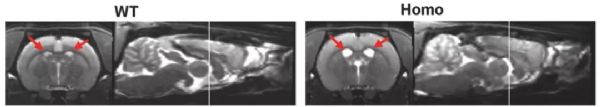

此外,这个大鼠模型还表现出由细胞凋亡和坏死性凋亡介导的神经元死亡,以及大脑皮层的严重萎缩,从MRI图像上可以观察到脑室扩大。而无论是转基因的“一代小鼠模型”[5],还是基因敲入的“二代小鼠模型”[6],都没有出现神经元的死亡或脑萎缩。